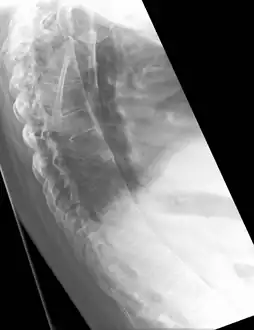

The earliest changes demonstrable by plain x–ray shows erosions and sclerosis in sacroiliac joints. Progression of the erosions leads to widening of the joint space and bony sclerosis. X-ray spine can reveal squaring of vertebrae with bony spur formation called syndesmophyte. This causes the bamboo spine appearance. A drawback of X-ray diagnosis is the signs and symptoms of AS have usually been established as long as 7–10 years prior to X-ray-evident changes occurring on a plain film X-ray, which means a delay of as long as 10 years before adequate therapies can be introduced.[21]

Lateral X-ray of the mid back in ankylosing spondylitis -

X-ray showing bamboo spine in a person with ankylosing spondylitis -